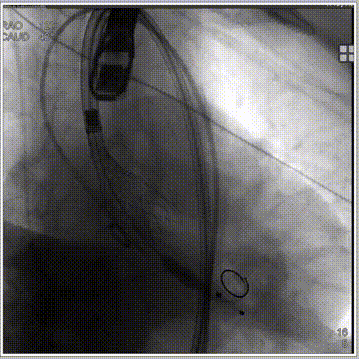

经左股动脉穿刺,置入6F股动脉穿刺鞘,将猪尾导管引导至主动脉根部,行主动脉造影。180bpm下置入23mm球囊扩张,沿导丝送入美敦力Evolut PRO经导管主动脉瓣膜系统,采用美敦力独有的commissual alignment技术,最大程度保护冠脉。递送系统顺利送入动脉系统并顺利过弓跨瓣,在采用世界先进的Cusp Overlap技术植入技术,最终目标位置完美释放,瓣膜立即工作,展开形态良好,无瓣周漏,无冠脉阻挡,无传导阻滞发生,术后无压差,血液动力学稳定,手术圆满成功。